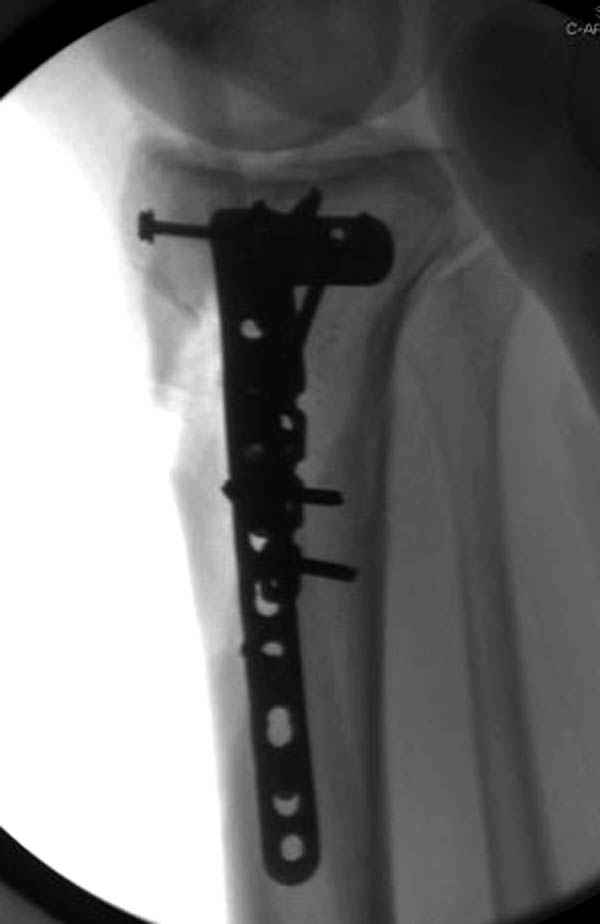

Трудно поверить, что разрекламированная Ортопедическая школа Восточной Украины позволяет такие странные снимки? На прямом снимке сохранен общий контур плато, но не известна судьба импрессии суставной поверхности. На полубоковой?, оставлен без репозиции задне-медиальный отдел, и навряд ли после такой фиксации можно удовлетвориться результатом.

Такая ситуация характерна для многих, когда принимается ошибочное решение, т.е пытаются фиксировать одним имплантом переломы двух мыщелков. Латеральная пластина приемлема только для тех случаев, когда сохраняется интактным медиальный диафизарный кортекс и отсутствует фрагментация на верхушке медиального перелома.

Здесь как раз тот случай, когда результат зависит не только от мастерства хирурга, но и от наличия современных методов исследования. Например, КТ которая поможет рассчитать направления шурупов и установку импланта. Кроме этого, поможет определиться с доступом.

На представленных предоперационных срезах КТ огромный задне-медиальный фрагмент расположен больше кзади, чем медиально. Для планирования, кроме поперечных срезов, надо ориентироваться на корональные срезы, которые укажут топографию верхушки медиального фрагмента.

При сложных переломах тибиал плато для своего рода Damage Control мы иногда применяем поэтапную тактику. Сперва оперируется одна сторона, а потом после рекондиции мягких тканей окончательный этап.

Если состояние мягких тканей позволяет, я бы предложил такой метод для вашего больного. Без предварительного планирования будет трудно, но шанс не надо упускать. Всего несколько дней после операции, и такая тактика лучше, чем недовольный молодой пациент.

Представленные снимки не информативны, нужны отдельные качественные снимки коленного сустава и голени без ротации.

Доступ к медиальной стороне задний или медиальный, через pes или в пространстве между medial gastroc мышцы.

Надеюсь, представленные снимки разных случаев помогут разобраться в тактике, и критика примется без личной обиды.